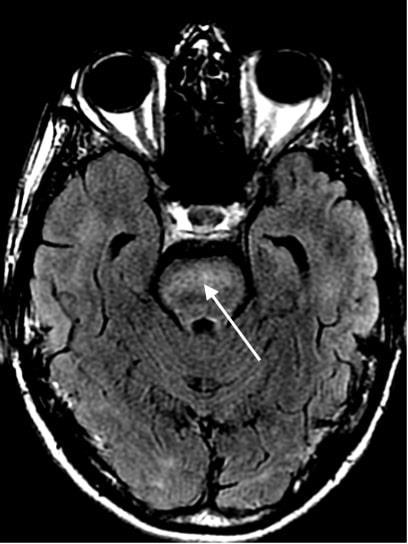

ATYPICAL PRESENTATION AND DIAGNOSIS OF AIDS-RELATED CMV ENCEPHALITIS

Erick Kawegere1, Tamara Goldberg1

1Mount Sinai Morningside-West Hospitals, Icahn School of Medicine at Mount Sinai, New York, NY, United States

Published in BMJ Case Reports, 2022. PMID: 36041775 35